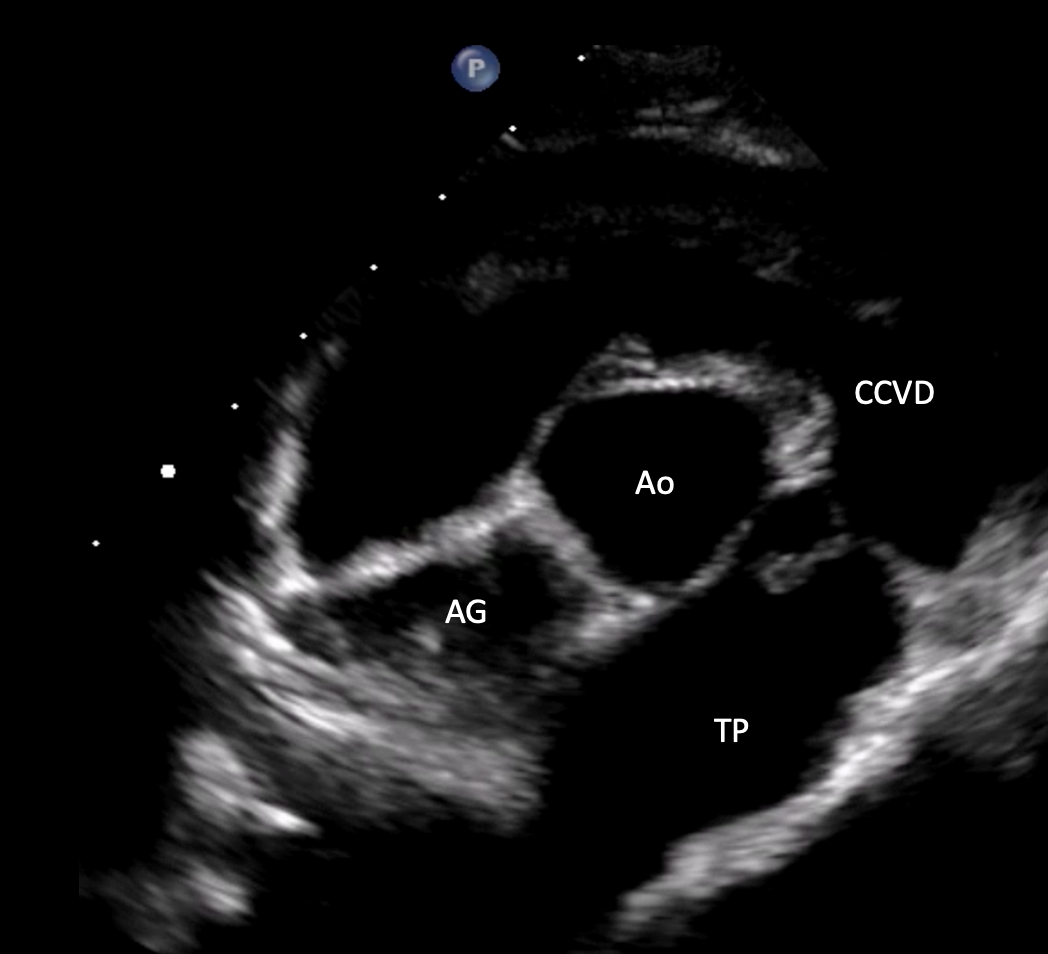

• Maîtriser la prise en charge des affections cardiaques congénitales les plus fréquentes chez le chien et le chat.

• Identifier, classifier et graduer les cardiopathies congénitales à partir des anomalies détectées en échocardiographie 2D, TM et Doppler.

• Interpréter de manière croisée les informations issues des différents modes échographiques (2D, TM, Doppler) pour affiner le diagnostic.

Analyse de cas cliniques illustrés par des images fixes et/ou des vidéos d’échocardiographie (2D, TM, Doppler).

Objectif : apprendre à repérer, décrire et interpréter les anomalies échographiques dans une démarche diagnostique rigoureuse, jusqu’à l’établissement de diagnostics différentiels.

Revue des bases en échocardiographie 2D, TM et Doppler appliquées aux cardiopathies congénitales.